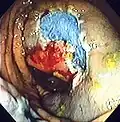

The first step is usually a digital rectal examination (DRE), to examine the tone of the anal sphincter and to determine if preparation has been adequate. A DRE is also useful in detecting anal neoplasms and the clinician may note issues with the prostate gland in men undergoing this procedure.[57] The endoscope is then passed through the anus up the rectum, the colon (sigmoid, descending, transverse and ascending colon, the cecum), and ultimately the terminal ileum. The endoscope has a movable tip and multiple channels for instrumentation, air, suction and light. The bowel is occasionally insufflated with air to maximize visibility (a procedure that gives the patient the false sensation of needing to take a bowel movement). Biopsies are frequently taken for histology. Additionally in a procedure known as chromoendoscopy, a contrast-dye (such as indigo carmine) may be sprayed through the endoscope onto the bowel wall to help visualize any abnormalities in the mucosal morphology. A Cochrane review updated in 2016 found strong evidence that chromoscopy enhances the detection of cancerous tumors in the colon and rectum.[58]